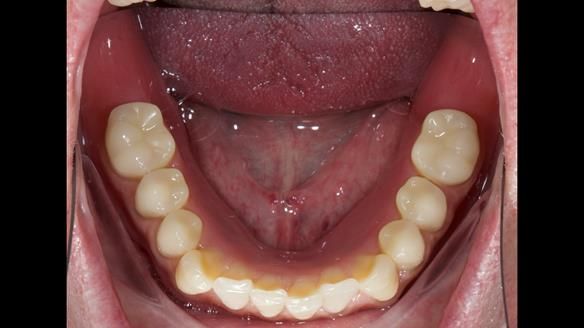

3. Both upper and lower dentures can be enhanced in appearance.

4. Heavy biting forces (bruxism) have worn down the dentures, likely contributing to the unsatisfactory new upper denture.

The detailed clinical situation and treatment process are outlined below, with clinical work provided by me and technical work by Rowan Garstang. New complete implant supported complete dentures were made. The new upper denture had ‘almost’ full palatal extension for the non-splinted implants following ITI guidelines. A decision was reached to retain the worn Kerator attachments, as their removal could potentially accelerate implant failure. The treatment spanned five visits for denture fitting and one review. Alisdair expressed great satisfaction with the treatment, noting a significant enhancement in his overall quality of life.